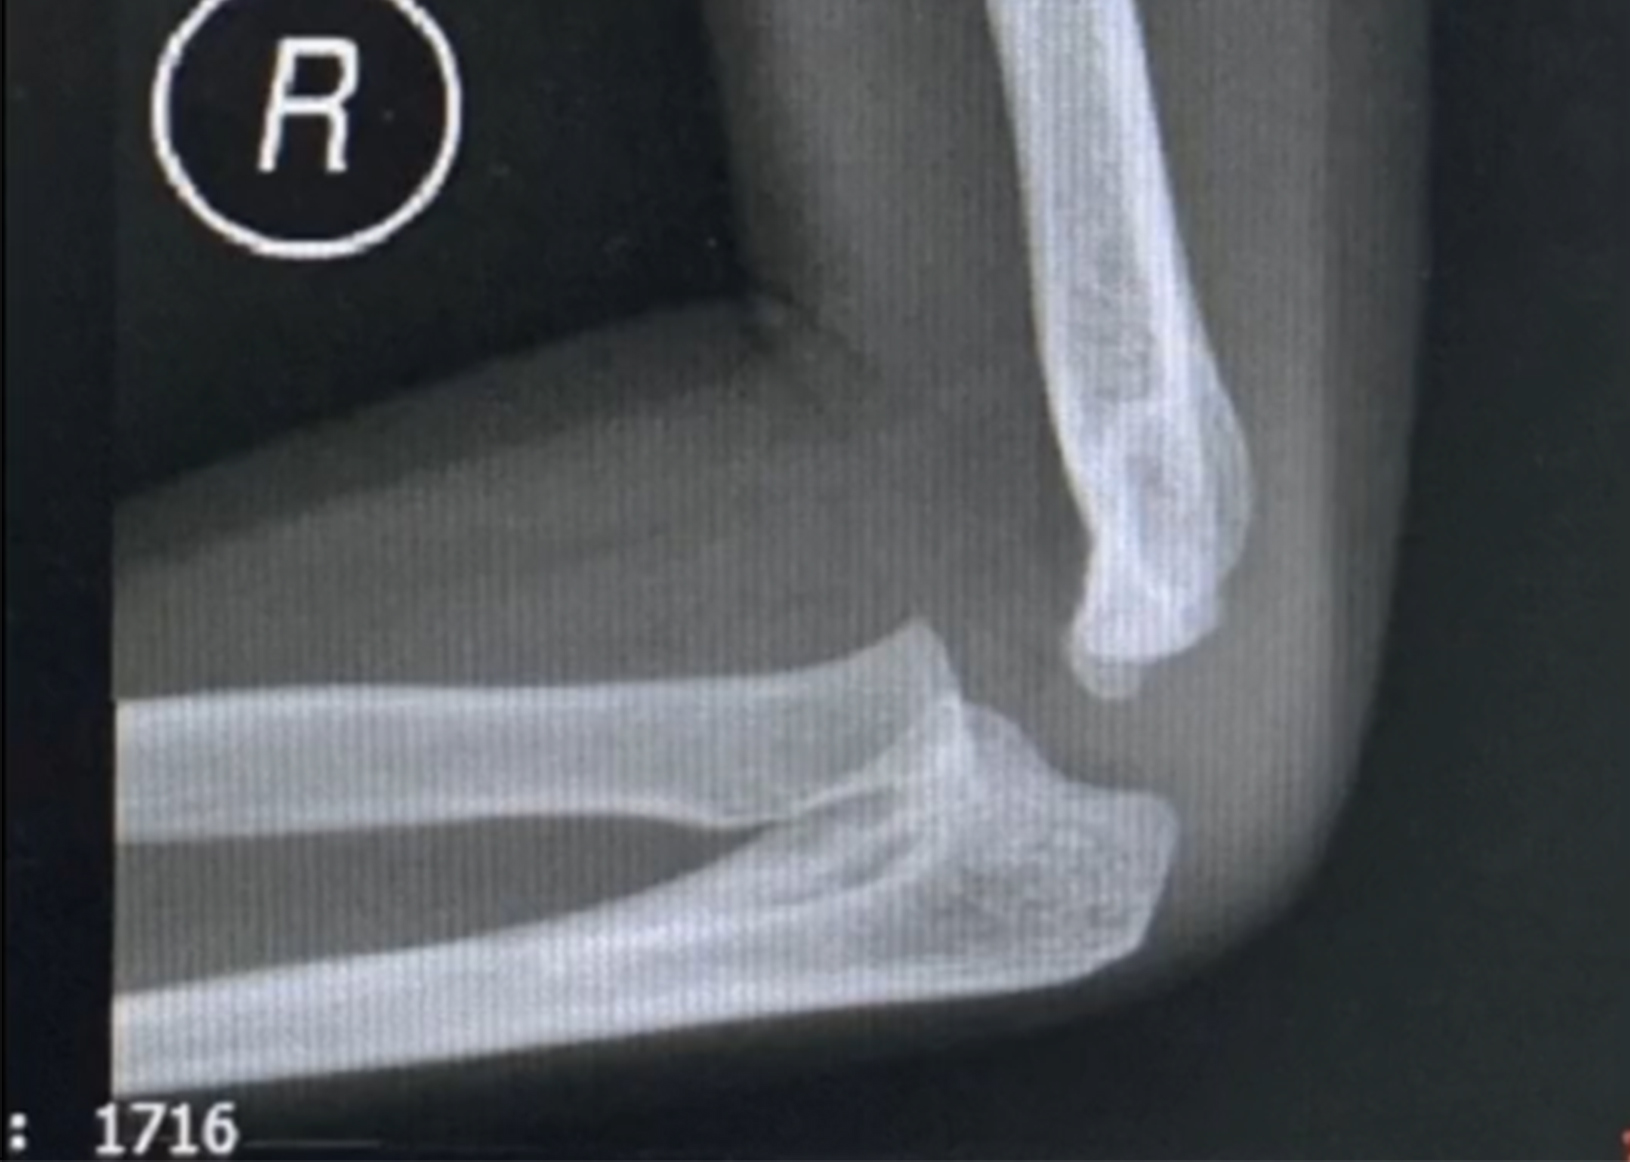

宝贝天生手掌不能朝上,微创手术后终于可以如愿以啦!

上尺桡关节融合